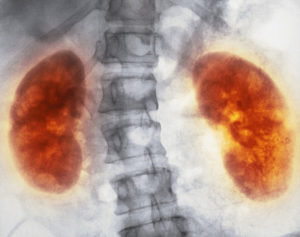

Для достоверной диагностики микронефролитиаза назначают сдачу клинических анализов крови и мочи, ультразвуковое сканирование мочевыводящих протоков, рентген. Эти методы дают высокую степень в обнаружении микронефролитиаза почек.

- УЗИ почек. Позволяет выявить изменения в структуре органа, уровень формирования болезни.

- Урография. Обнаруживает песок на начальном этапе формирования.

Для диагностики данного заболевания, помимо общих анализов мочи и крови, применяется метод ультразвукового исследования.

УЗИ обнаруживает местоположение микролитов размером до 2 мм и возможные аномалии развития мочеполовой системы. Информативным является и контрастное рентгенологическое исследование, которое позволяет обнаружить оксалатные микролиты, которые не видны при УЗИ.